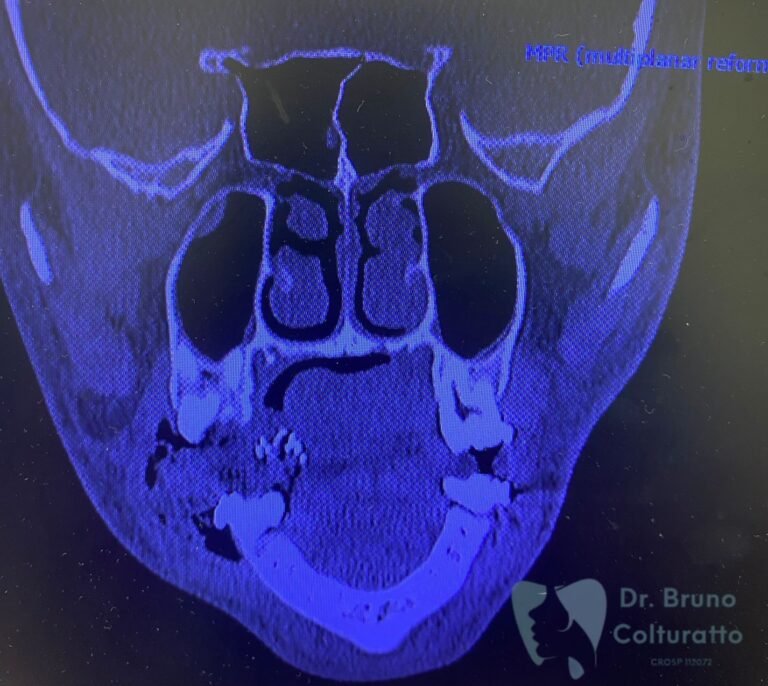

A Patologia Oral e Maxilofacial é a especialidade responsável pelo diagnóstico e tratamento de doenças que afetam a boca, mandíbula e estruturas faciais. Atua na identificação de lesões, cistos e tumores, garantindo diagnóstico preciso e tratamento adequado para preservar a saúde bucal e geral do paciente.